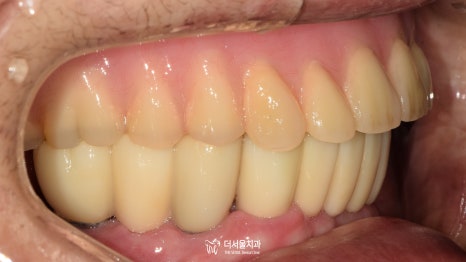

며칠 뒤, 크라운 세팅을 위해 다시 오셨습니다.

예쁘게 제작된 보철을 올려드리며

사후관리까지 약속드린 후에 마무리를 했습니다!

불편한 틀니를 교체하기 위해

하악 네비게이션 임플란트 를 진행했던 증례였습니다.